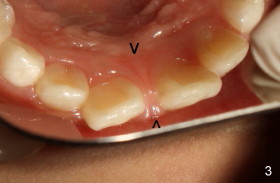

Eight-year-two-month girl has diastema between the maxillary central incisors.  It appears that the upper labial frenum (Fig.3 arrowheads, mirror view) bisects the interdental papilla (Fig.5).  Frenectomy is planned before orthodontic closure of the diastema.  Fig.4 is pre-op X-ray. Five months later, the diastema is closed.  The frenum appears to recede upward (Fig.6).  The bisected papilla seems to fuse (Fig.6,7).  Although the diastema has tendency to relapse when power chains are not used, fixed lingual retainer is planned to prevent the relapse when brackets are to be removed.  It appears that frenectomy is not so highly necessary for this purpose.